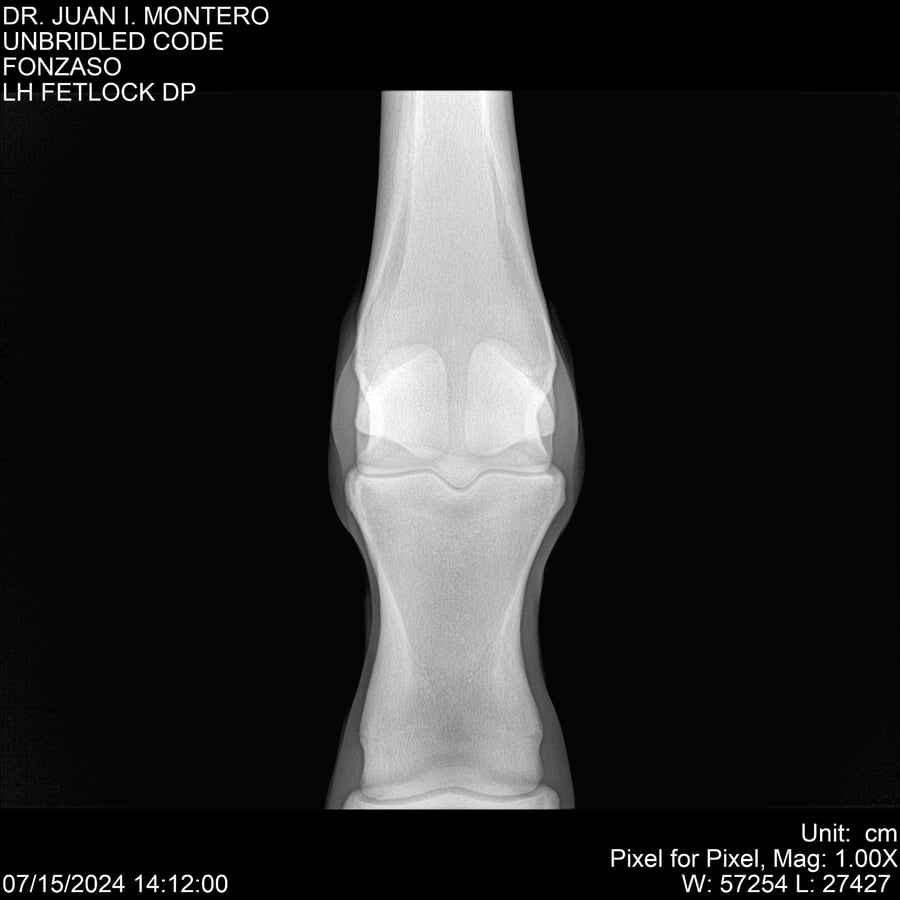

• Empresa: Abelenda N. R., Walter Hugo